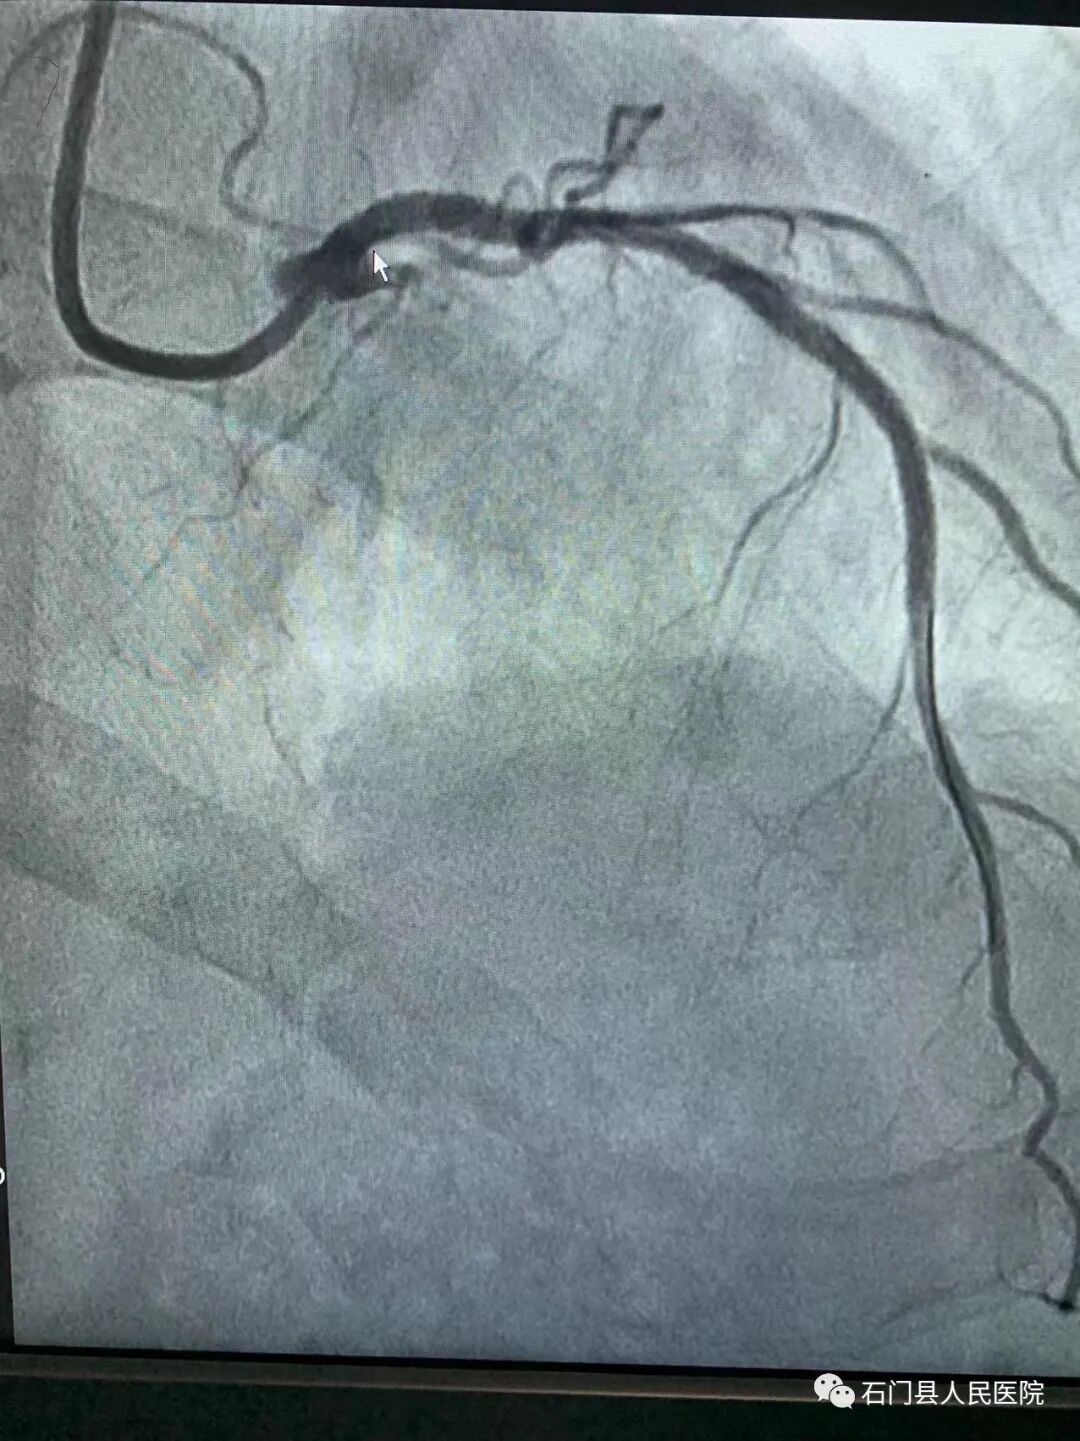

经桡股动脉冠脉造影术、支架植入术、球囊扩张术、主动脉支架置入术,心脏永久起搏器植入术、心脏射频消融术;房间隔缺损封堵术,左心耳封堵术。